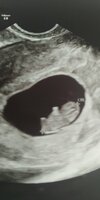

Wróciłam!!! Poślizg prawie 2h. Ale warto było czekać. Wg usg 6+0 (wg om 6+6),

jest zarodek i ❤

Niewiem czy pamiętacie ale byłam równo tydzień temu i był sam pusty pęcherzyk. A dzisiaj już wszystko